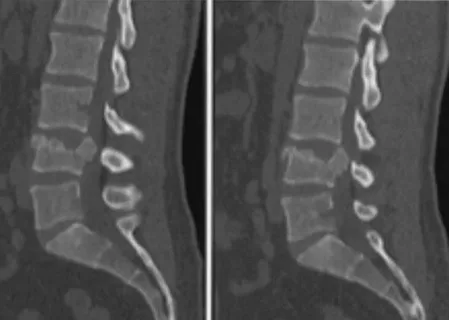

Understanding Burst Fractures and Spine Care | Spi...